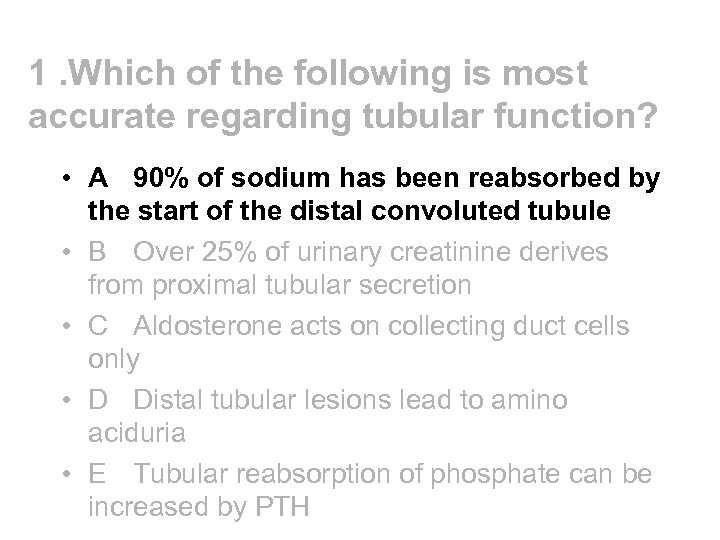

1. Which of the following is most accurate regarding tubular function? • A 90% of sodium has been reabsorbed by the start of the distal convoluted tubule • B Over 25% of urinary creatinine derives from proximal tubular secretion • C Aldosterone acts on collecting duct cells only • D Distal tubular lesions lead to amino aciduria • E Tubular reabsorption of phosphate can be increased by PTH

1. Which of the following is most accurate regarding tubular function? • A 90% of sodium has been reabsorbed by the start of the distal convoluted tubule • B Over 25% of urinary creatinine derives from proximal tubular secretion • C Aldosterone acts on collecting duct cells only • D Distal tubular lesions lead to amino aciduria • E Tubular reabsorption of phosphate can be increased by PTH

1. Which of the following is most accurate regarding tubular function? • A 90% of sodium has been reabsorbed by the start of the distal convoluted tubule • B Over 25% of urinary creatinine derives from proximal tubular secretion • C Aldosterone acts on collecting duct cells only • D Distal tubular lesions lead to amino aciduria • E Tubular reabsorption of phosphate can be increased by PTH

1. Which of the following is most accurate regarding tubular function? • A 90% of sodium has been reabsorbed by the start of the distal convoluted tubule • B Over 25% of urinary creatinine derives from proximal tubular secretion • C Aldosterone acts on collecting duct cells only • D Distal tubular lesions lead to amino aciduria • E Tubular reabsorption of phosphate can be increased by PTH

PCT - most aminoacids, Ca and PO 4 reabsorbed; creatinine secreted (accounting for up to 15% urinary creatinine) • proximal tubular secretion of creatinine does not account for more than 25% urinary creatinine (except in advanced renal failure) • distal tubular lesions do not lead to aminoaciduria • tubular reabsorption PO 4 not increased by PTH (PTH acts to raise serum calcium and to lower serum PO 4) • Aldosterone acts on connecting segment and CCD

PCT - most aminoacids, Ca and PO 4 reabsorbed; creatinine secreted (accounting for up to 15% urinary creatinine) • proximal tubular secretion of creatinine does not account for more than 25% urinary creatinine (except in advanced renal failure) • distal tubular lesions do not lead to aminoaciduria • tubular reabsorption PO 4 not increased by PTH (PTH acts to raise serum calcium and to lower serum PO 4) • Aldosterone acts on connecting segment and CCD